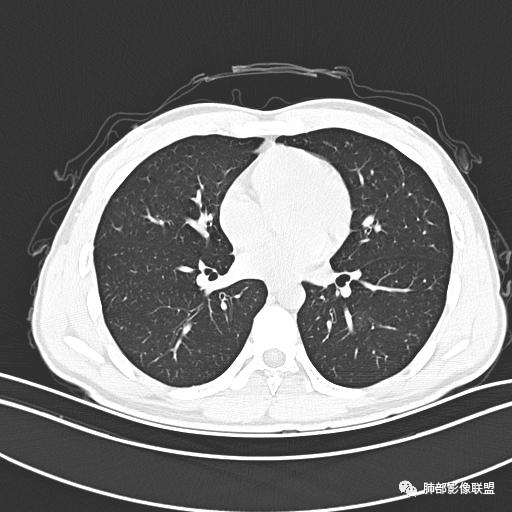

小强:青年,发热,皮疹;双肺散在结节,周围磨玻璃,点晕征,疱疹病毒感染,鉴别荚膜组织胞浆菌,结核。 大雄:青年,急性起病,发热伴全身皮疹2天,抗病毒治疗体温有下降。双肺随机分布大小不等类圆结节,“点晕征”。考虑水痘-疱疹病毒(VZV)血播询问接触史,查体皮疹分布以及形态基本可诊断。 王开金江津中心医院呼吸科:青年男性,起病急,病程短,以发热,皮疹为首发症状,感染指标以单核细胞升高为主,胸部ct双肺多发结界,周围有晕,点晕表现,随机分布,同意於老师意见,水痘疱疹病毒血流感染累及肺。 王秀仙:双肺多发大小不等结节,周围有晕,边缘模糊,呈点晕征表现。青年,急性起病,发热伴全身皮疹2天,抗病毒治疗体温有下降。考虑疱疹病毒。鉴别荚膜组织胞浆菌。 傅昌瑜:19岁男性,发热、全身皮疹2天,单核细胞增高,双肺多发结节,结节边缘见边界不清磨玻璃影。点晕征+发热、全身皮疹+单核细胞增高——考虑水痘-带状疱疹病毒肺炎。 一切∮随缘:年轻男性,发热,皮疹两天,实验室,CRP,PCT增高,影像:双肺多发散在磨玻璃结节,边界欠清,大小不等,呈点晕征改变,以血管束周围分布为主,局部血管束略增粗,其它无明显改变,考虑:1:病毒性肺炎(水痘疱疹病毒?不知道皮肤有无改变)2:真菌(组织胞浆菌,血管侵袭性肺曲霉)3:GPA4:寄生虫(实验室没有看到嗜酸细胞增高) 赵山河:双肺散在结节,周围有晕,边缘模糊,呈点晕征表现。青年,急性起病,发热伴全身皮疹2天,抗病毒治疗体温有下降。考虑水痘—疱疹病毒感染。洪桥爱:青年男性,发热、皮疹2天,伴瘙痒,皮疹于面部首发,之后进展至全身,虽然没有对皮疹进行描述,但是从出疹时间及皮疹进展情况,伴瘙痒,应该就是个水痘患者;CT提示双肺随机分布结节影,部分结节伴有边界不清晕征,考虑水痘血播肺。 刘强:年轻男性,急性起病,皮疹,发热,抗感染治疗体温下降,说明有效。影像表现为散在点晕征,感染类疾病谱(疱疹病毒,真菌,结核),结合年龄,皮肤皮疹,考虑水痘-疱疹病毒性肺炎。 小兜:男性,19岁,发热皮疹两天,颜面部至全身,CRP,降钙素及单核增高。CT示双肺散在小结节,周围伴磨玻璃影,点晕征,考虑为水痘-带状疱疹病毒(varicella-zoster virus,VZV)肺炎 必有路:青年,皮疹+发热+“点晕征”→水痘-疱疹病毒(VZV) 许慧良:青年男性患者,发热、皮疹2天,体温最高38.5℃,第3天皮疹扩展至全身,伴瘙痒,胸部CT:双肺多发随机分布的小结节,结节周边见边界模糊的晕征,考虑水痘病毒感染流心明智:男,19,急性起病,发热伴全身皮疹2天。出疹顺序头→全身,抗病毒有效。胸部CT:两肺多发大小不等类圆形实性小结节影,随机分布,结节周围环绕GGO,边界模糊,呈点晕征。出疹特点是关键,未提示。考虑:血播病毒性肺炎,水痘-疱疹病毒?麻疹?鉴别荚膜组织胞浆菌、TB、血管炎、寄生虫等。 浪迹天涯:病灶多为5-10mm大小结节,结节周围可见磨玻璃样的晕环,常多发,可分布于肺内任何区域,考虑水痘—带状疱疹病肺炎如果短时间内有新的一个区域浸润,更加能说明,